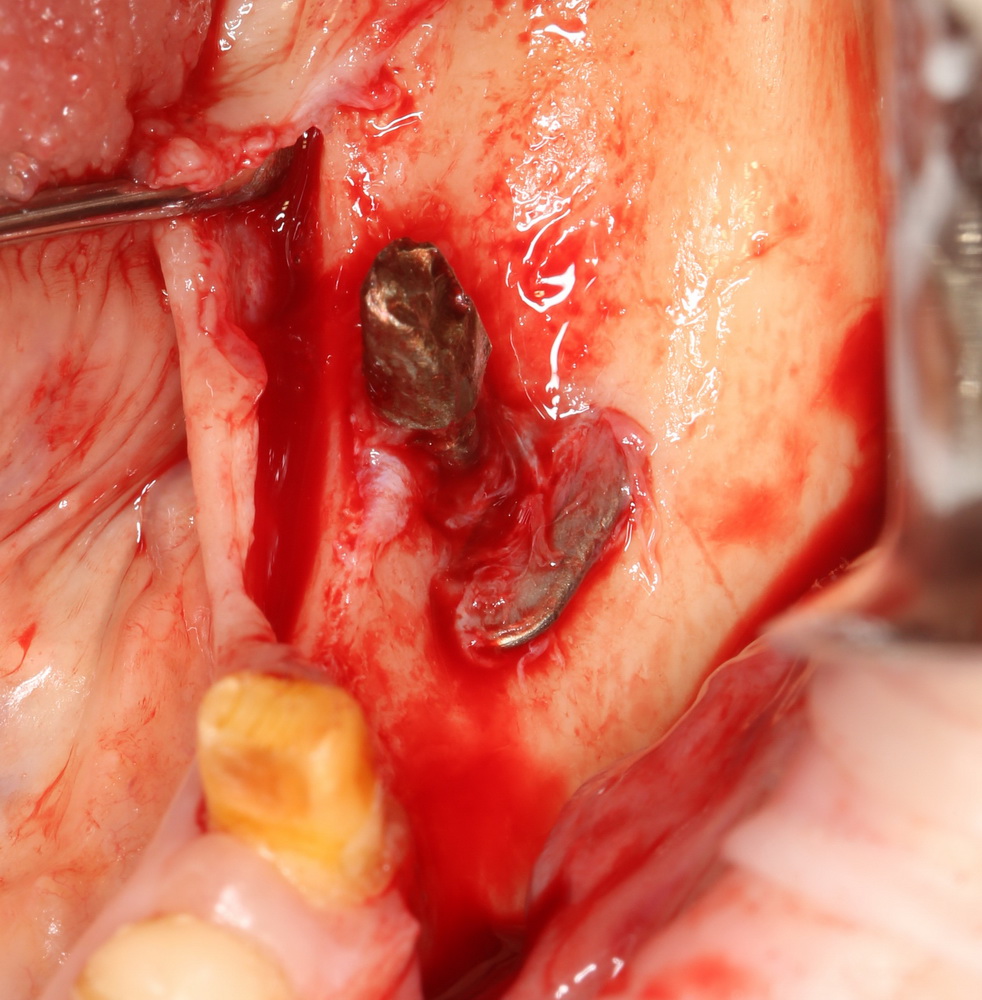

Как правило, вся работа с этими имплантами сводится к их удалению:

Затем — восстановление утраченных объемов костной ткани и нормальная, винтовая имплантация.

К слову сказать, базальные импланты не интегрируются, а удерживаются, исключительно, за счет своей формы:

Мы вынуждены их удалить. И теперь представьте, как будет проходить такое удаление и с каким дефицитом костной ткани мы, в итоге столкнемся. Что вообще делать дальше? Девушка плачет.